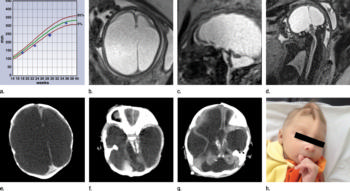

Figure 2. (a) Axial, (b) sagittal, and (c) coronal fetal T2-weighted MR images were obtained in a 29-year-old woman with confirmed Zika virus infection, initially seen for characteristic rash at 12 weeks of gestational age. (d) Axial postnatal CT image and (e–g) axial and (h) coronal T2-weighted MR images were obtained in her male neonate. The fetal MR images obtained at 34 weeks (a–c) show asymmetrical ventriculomegaly with a septation in the right occipital horn (arrowhead on a), small frontal lobes, thinning of the occipital parenchyma (left worse than right), underdeveloped sylvian fissures, and regions of thickened cortex, as in the right frontal lobe, which is suggestive of polymicrogyria (arrow on a). There is abnormal, increased signal intensity in the white matter. The postnatal CT image (d) obtained in the 22-day-old neonate shows punctate calcifications at the gray matter–white matter junction and asymmetrical ventriculomegaly. The T2-weighted MR images obtained at 26 days (e–h) show septation in the ventricle (arrowhead on e). Note how the right ventricle has relatively decreased in size compared with the prenatal image, whereas the left ventricle has increased in size. Under-rotation of the hippocampus (arrowheads on f) is demonstrated. There is clear asymmetry of the gyral pattern on g, which is relatively smooth in the left occipital region, with abnormal folds in the right occipital and frontoparietal regions (arrows on g). Subependymal cysts are visualized on h, which are not seen on fetal MR images.

Figure 3. Images obtained in the case of a 34-year-old woman with confirmed Zika virus infection, initially seen for a rash at 8 weeks of gestation. Fetal head cir¬cumference was in the normal range at 12 and 16 weeks (5.8 cm and 11.9 cm, respectively) but then decreased to the 10th percentile at 22 weeks and was below the 3rd percentile in subsequent imaging examinations. (a–h) US images were obtained at 30 weeks. Head circumference on the axial image (a) measured 24 cm (˂2.3 percentile, corresponding to a gestational age of 26 weeks 3 days). Note the open sylvian fissures and relatively smooth cortex, which are abnormal findings at this gestational age. Oblique axial image (b) shows cerebellar calcifications (seen as the echogenic outer contour of the cerebellar hemispheres) and inferior vermian hypoplasia with associated enlarged cisterna magna. A sagittal transvaginal image (c) shows calcifications in the basal ganglia (arrowheads) and more bulky calcifi¬cation at the gray matter–white matter junction. Another sagittal transvaginal image (d) shows a relatively small corpus callosum (arrows). A coronal image (e) shows cortical and subcortical white matter calcifications in a linear pattern. The gyral pattern is abnormal, which is suggestive of polymicrogyria. A sagittal Color Doppler image (f) shows a stretched appearance of vessels coursing into the posterior fossa. An oblique axial grayscale transvaginal image in the posterior fossa (g) shows heterogeneous material in the confluence of sinuses due to blood clot (arrow). A three-dimensional US image of the face (h) shows a sloping forehead, compatible with frontal lobe hypoplasia. (i) Axial and (j) sagittal fetal MR images obtained at 29 weeks show atrophic frontal lobes, wide sylvian fissures, enlarged posterior fossa, abnormal gyral pattern, prominent cerebrospinal fluid spaces, and inferior vermian hypoplasia. On (i), note the diffuse hypointense and undersulcated cortex, which is suggestive of mineralization and polymicrogyria. The hypoplastic corpus callosum can be seen on the sagittal view (j), as well as the inferior vermian hypoplasia, en¬larged cisterna magna, and heterogeneous signal intensity in the confluence of sinuses. There is a subjectively thin spinal cord. (k) Postnatal axial MR image obtained at 81 days shows small frontal lobes and cortical thickening. The choroid plexi are enlarged. (l) Photograph of the neonate after birth.

High-res (TIF) version

Figure 4. Images obtained in the case of an 18-year-old woman, first seen for rash at 10 weeks of pregnancy, with confirmed Zika virus infection. US findings obtained at 20 weeks of gestational age were reportedly normal, with normal head circumference of 17.5 cm. At 37 weeks of gestational age, (a) sagittal transvaginal and (b) coronal transabdominal US images obtained with the head upside down show a small head circumference (26.4 cm, corresponding to 28 weeks 5 days, below the 3rd percentile), moderate ventriculomegaly with dense intracranial calcifications (arrowheads on a), and abnormal head shape with flattened appearance and thickened skin (arrow on a). On the sonogram, it is difficult to precisely localize the calcifications, given the thin parenchyma. (c, d) Axial bone window CT images, (e) sagittal localizer CT image, and (f–h) axial CT images show microcephaly with cerebral atrophy, and, despite ventriculomegaly, the extra-axial cerebrospinal fluid spaces are still prominent. The hypoattenuating calcifications are predominantly located in the subcortical white matter at the gray matter–white matter interface. There is markedly abnormal skull shape with some eversion of the bones at the suture sites (particularly frontoparietal sites), with redundant skin folds (particularly in the parieto-occipital region). (i) Sagittal T1-weighted, (j, k) coronal T2-weighted, and (l) axial susceptibility-weighted MR images obtained at 1 month of age show an undersegmented midbrain, severe microcephaly, open sylvian fissures, and polymicrogyria. The dense calcifications are evident on the susceptibility-weighted image. On the sagittal images (a, e, i), note the small supratentorial compartment and associated skull deformity.